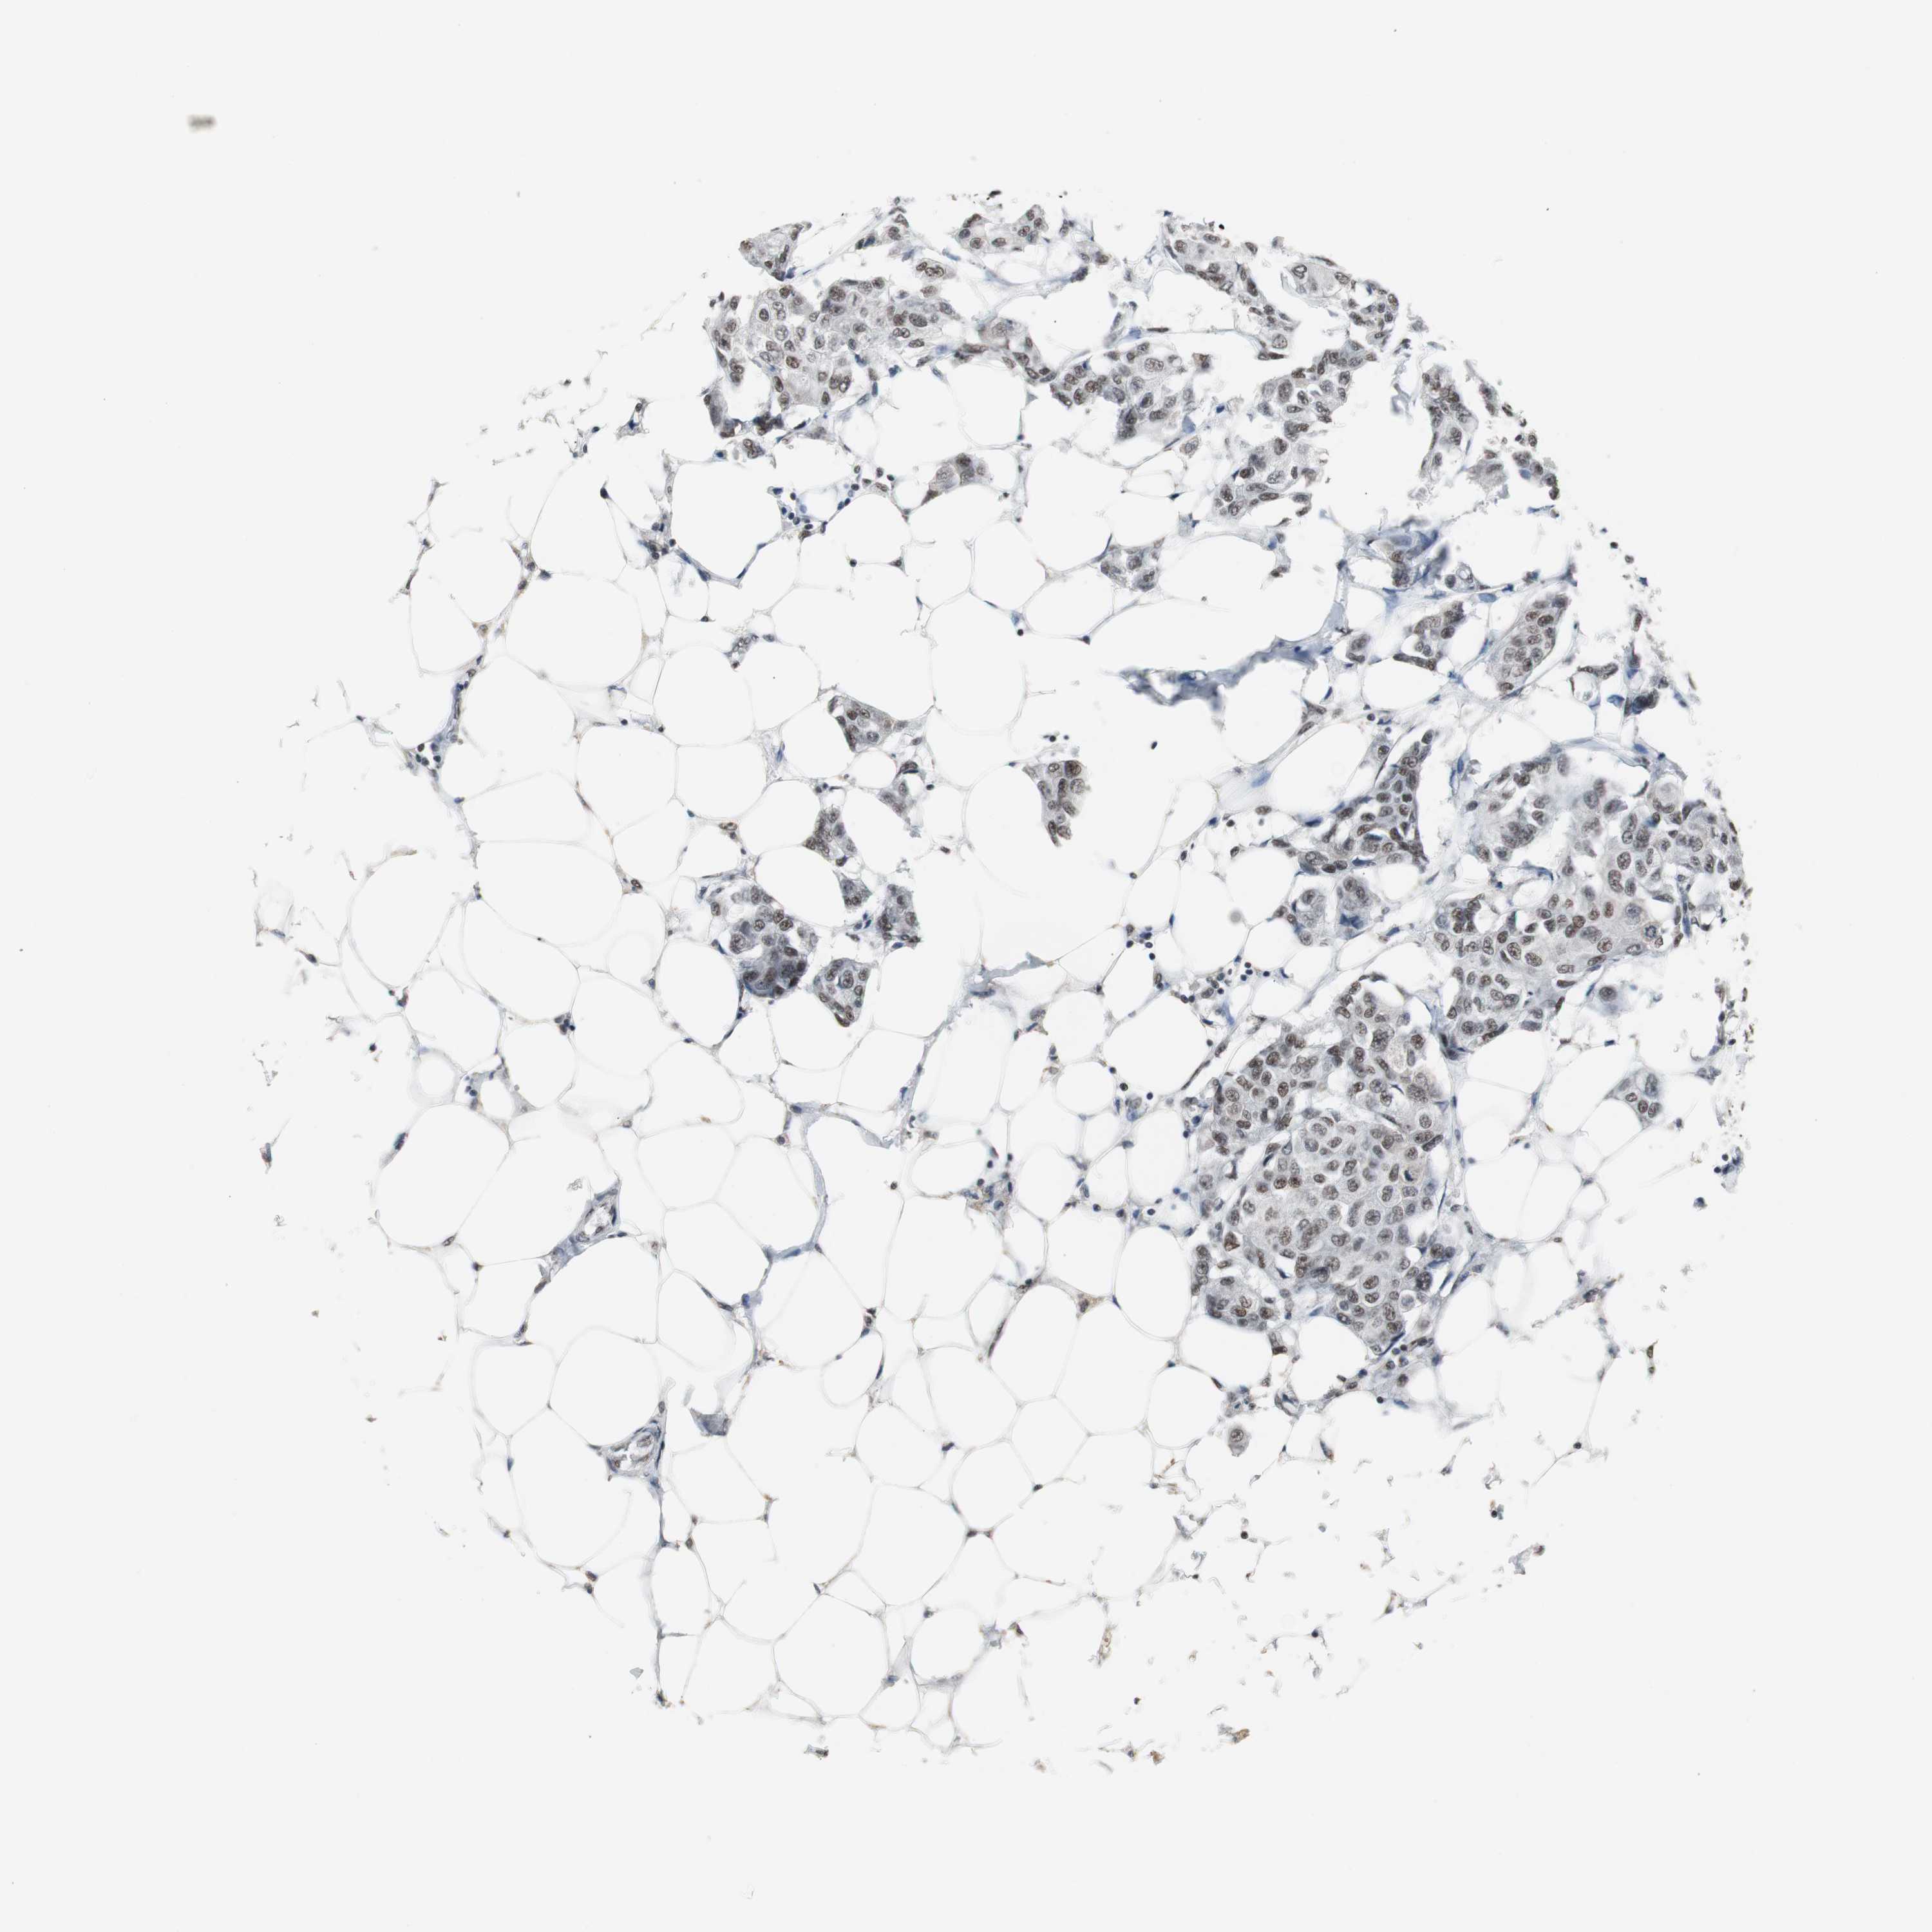

CANCER BREAST CANCER Show tissue menu

BRCA TCGA BRCA VALIDATION PROTEIN EXPRESSION